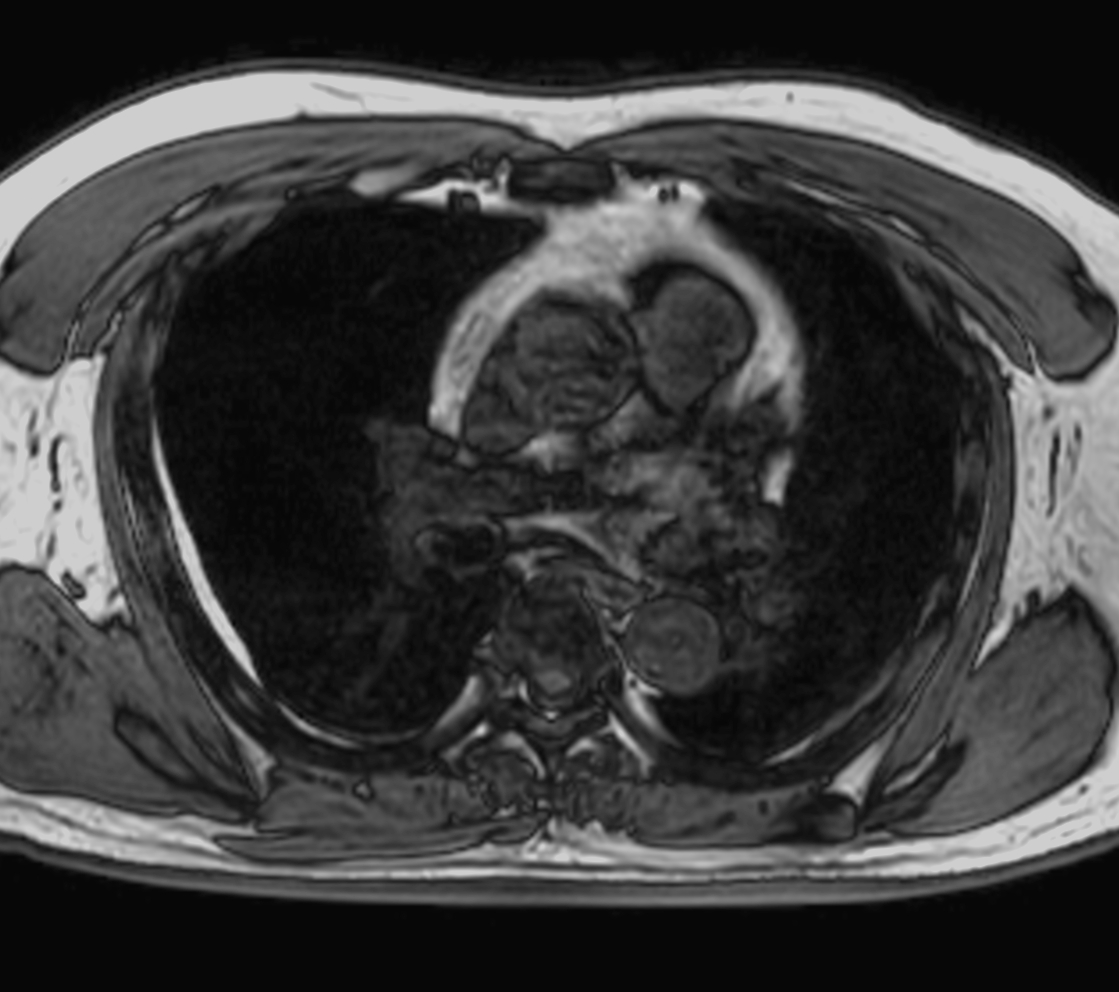

Axial T2w TSE - Black Blood

Axial T2w STIR - Black Blood

Axial MultiVane XD - T2w SPIR